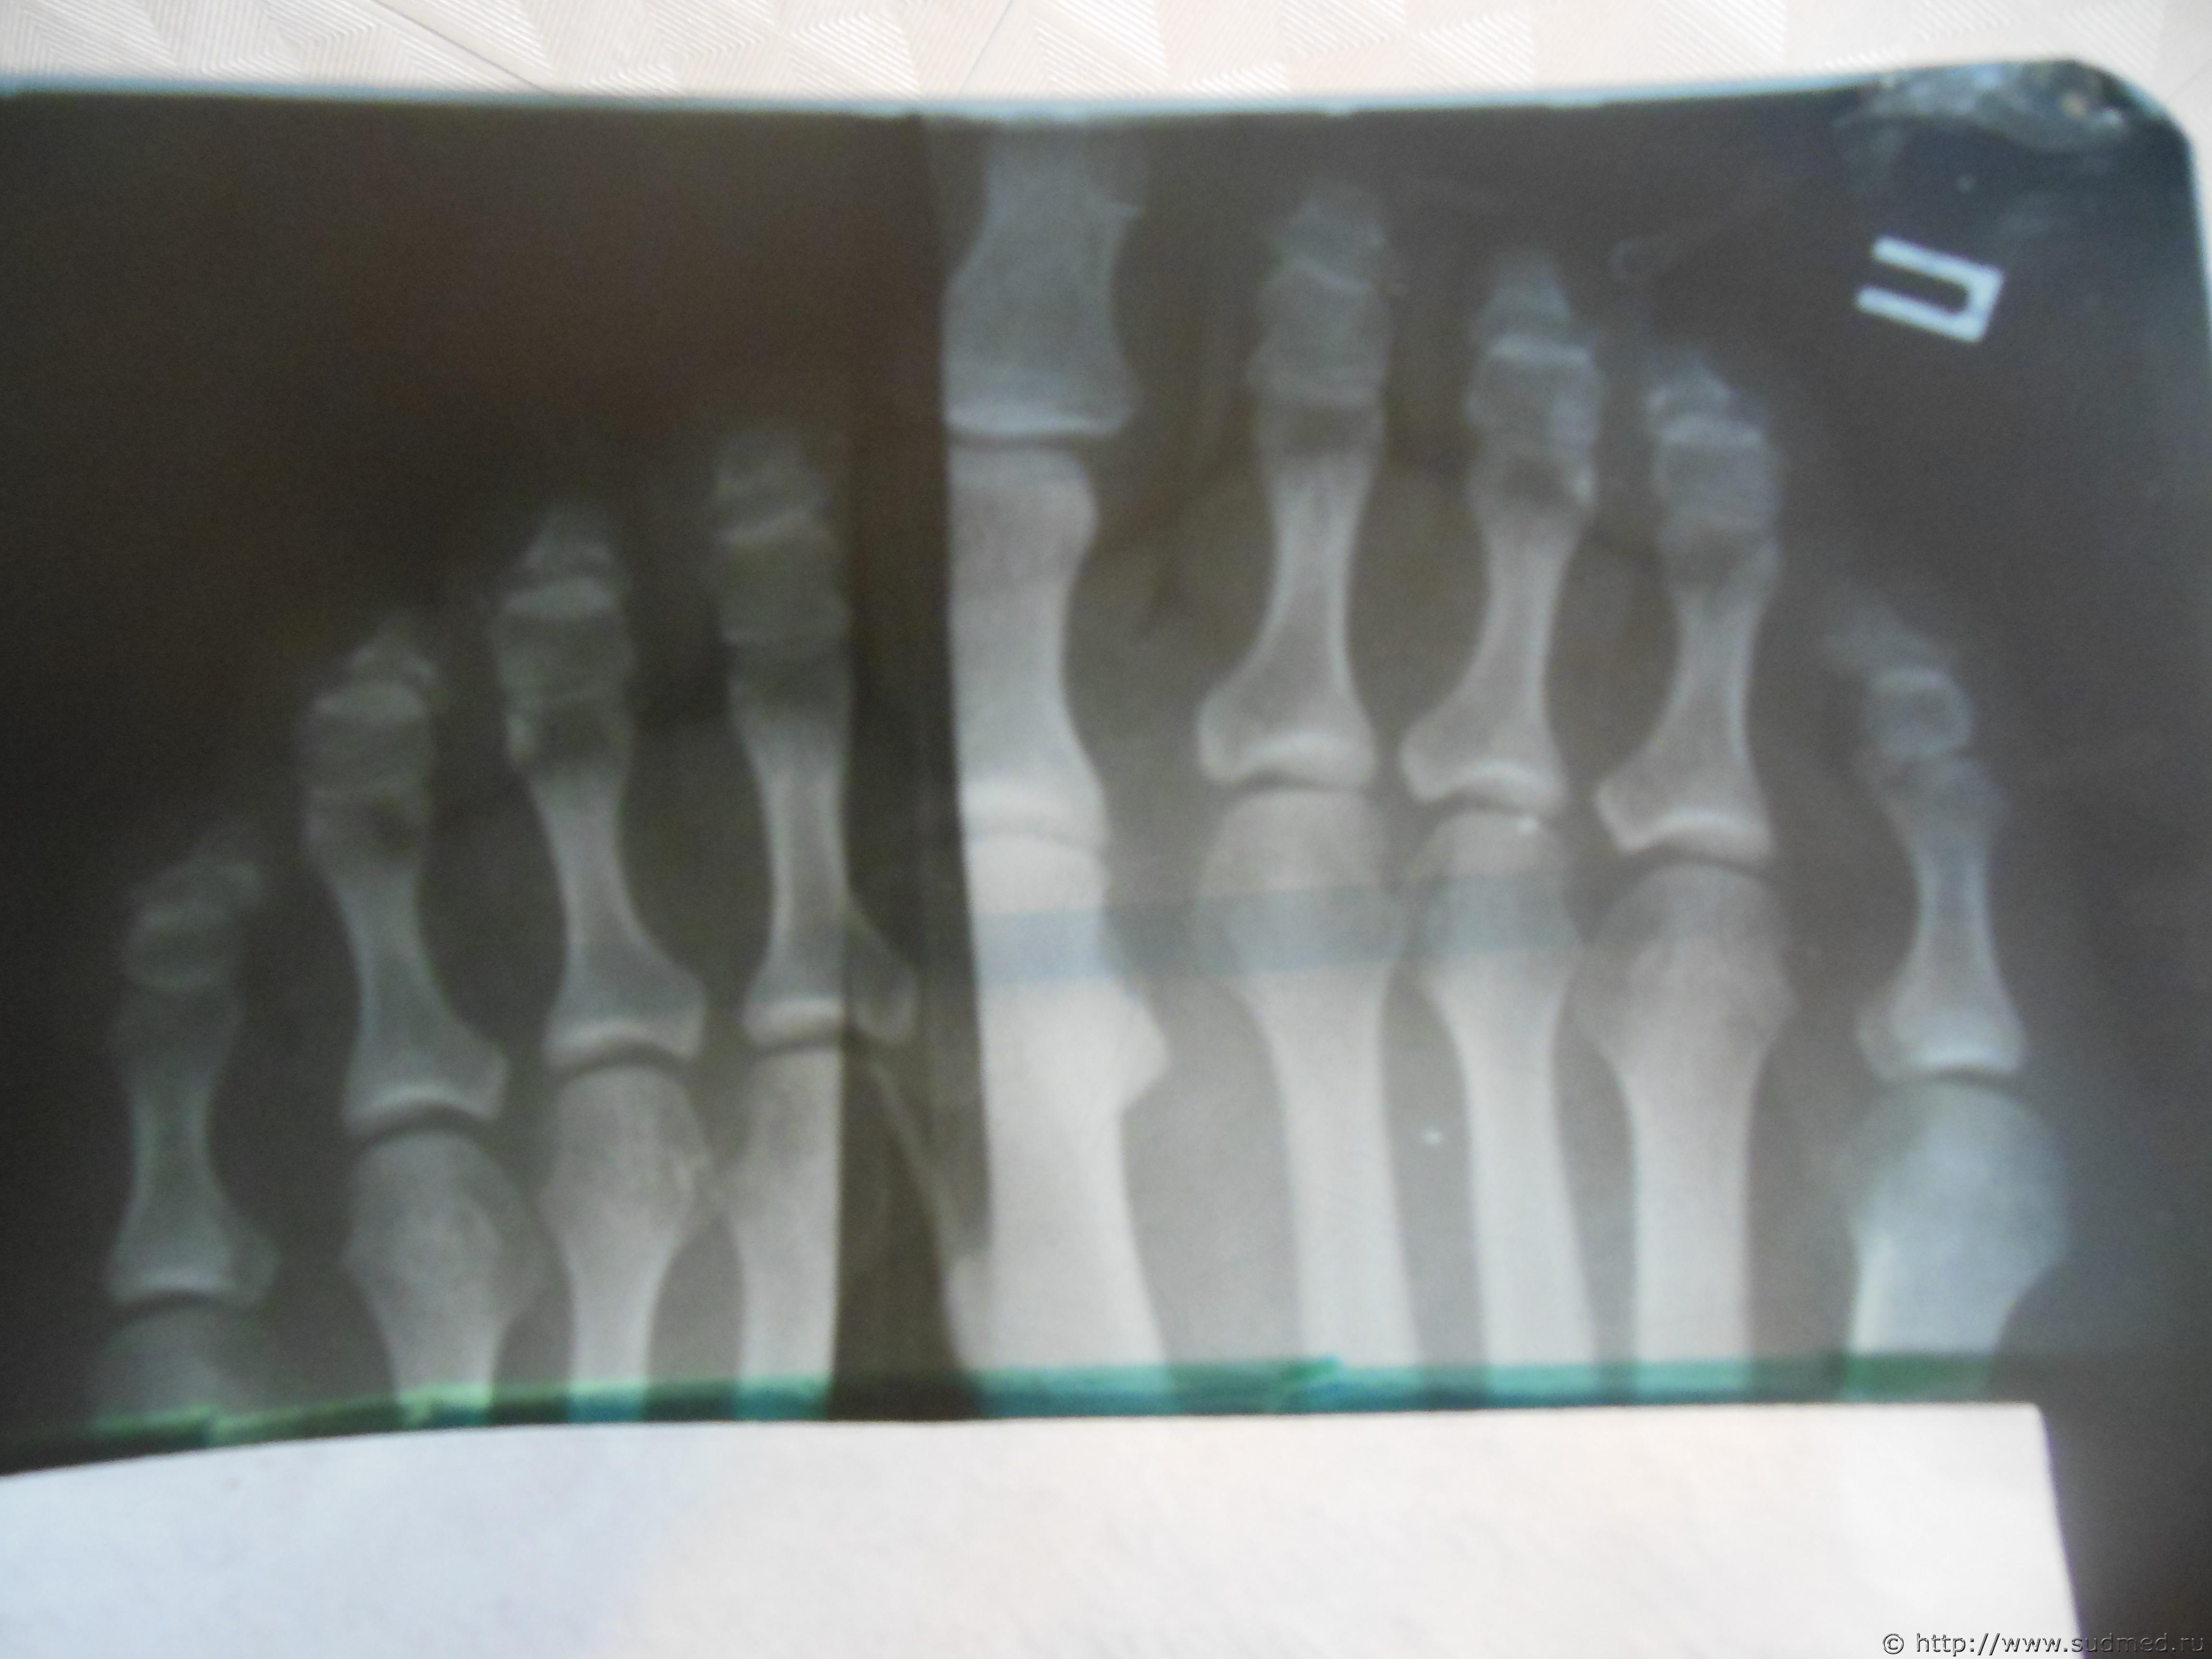

Судебная медицина - Прикрепленное изображение

Мог ли такой перелом быть от удара ноги.

Мог.

Такой перелом мог образоваться от удара ногой по Вашему мизинцу.

Какой степени тяжести травма?

Практически однозначно - вред здоровью средней тяжести (согласно п.7.1 приложения к Приказу Минздравсоцразвития от 24.04.08г. №194н). Для Вас будет лучше, если Вы не станете спешить завершать лечение в медицинском учреждении ранее 21 дня с даты травмы.